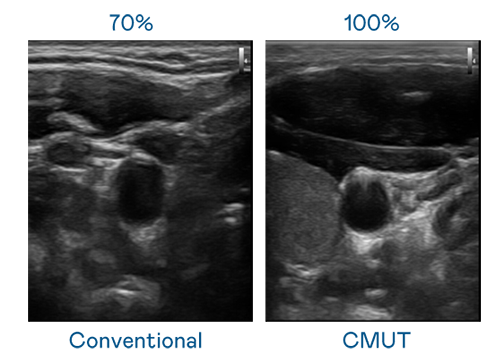

CMUT 技术是一种用电容式微机电元件来产生超音波讯号的技术。与传统 PZT 压电式技术相比,CMUT 频宽增加 30%,更宽频的超音波讯号让影像解析度大幅提升,是实现高影像品质医疗超音波扫描、促进精准医疗发展的关键技术。

大频宽带来超清晰影像

超音波影像的解析度高低,首先取决于探头能发出的讯号频宽。40001百老汇 CMUT 可提供高清晰的超音波讯号,提供高频宽、高灵敏度、影像纹理细节更高的超音波影像,协助医护人员缩短影像判读时间及利用精准的医疗影像进行诊断。